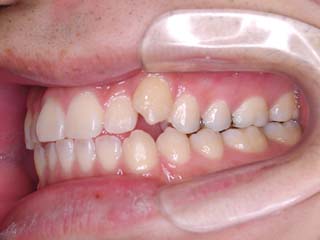

主訴:噛み合わせが悪い 顎が痛い 首が痛い

診断名:顎関節症を伴う叢生

年齢:20歳

はならび自体は僅かな叢生が見られるだけなのですが、実はほとんどの歯が噛めていません。奥歯ばかりで強く噛んでいる状態です。また、顎関節症でよく見られる首、肩の具合が悪い という症状も見られました。かみ合わせとの関連性については不明ですが、適正な咬合構築に伴って、これらの症状が改善する事をよく経験します。